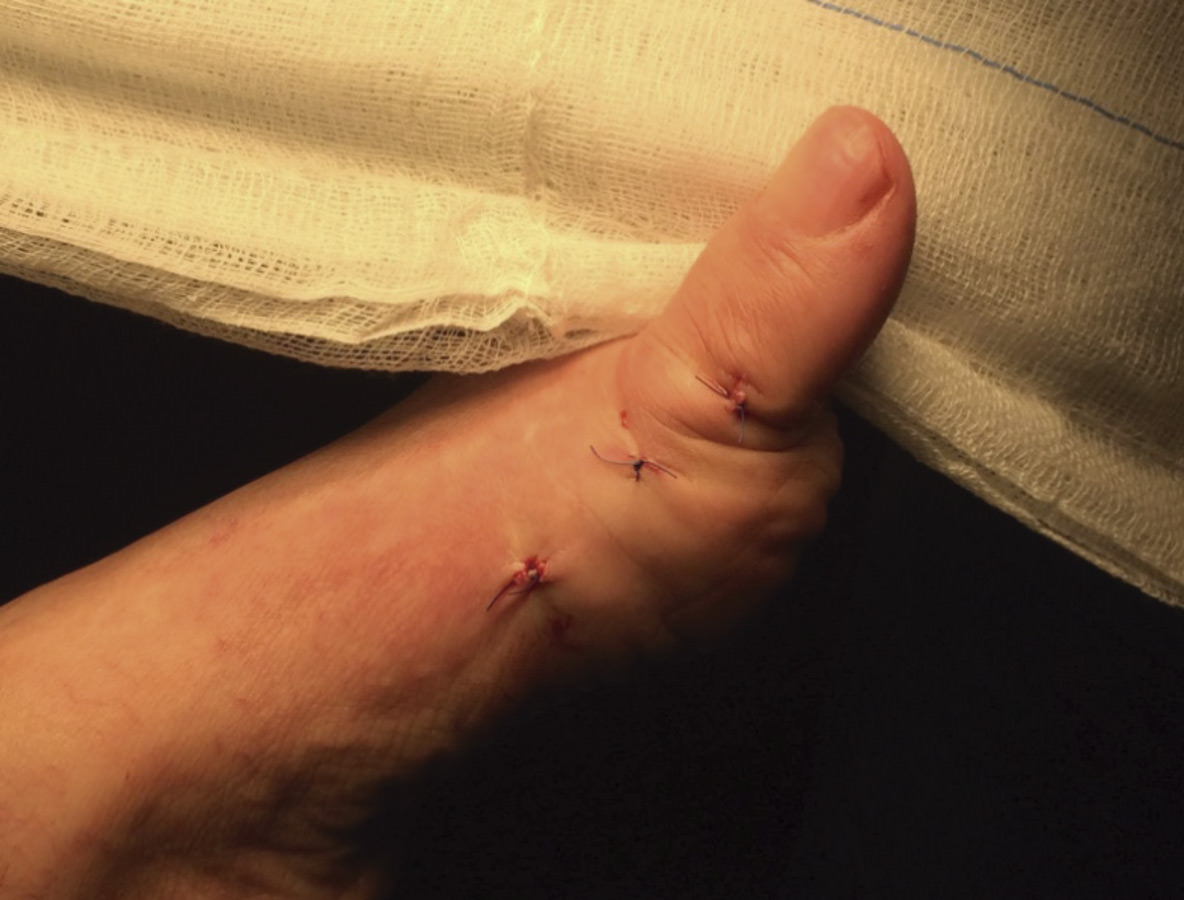

Figura 4. Los 3 portales necesarios para la artrodesis percutánea de la articulación metatarsofalángica del primer dedo. El portal más proximal y el más distal se utilizan para la introducción de los tornillos canulados.

La fijación de la artrodesis se realizará mediante 2 tornillos canulados de 3 mm de diámetro a través de las agujas. Utilizamos tornillos a compresión de doble rosca sin cabeza.

En casos con desaxaciones severas, se puede alinear los huesos a través del portal o portales liberando la cápsula articular y manipulando de forma externa para obtener una correcta alineación.